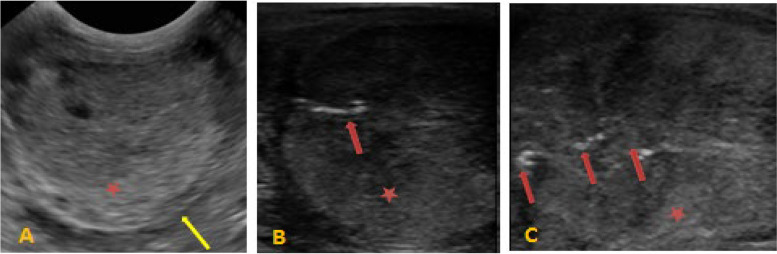

Before intra-testicular zinc gluconate injection, ultrasonography of the scrotal contents revealed homogeneous and mildly echogenic testicular parenchyma with no abnormalities in the epididymides, testes, or spermatic cords (Fig. 2A). However, at the end of the study period (day 60), noticeable alterations in testicular echo density were observed, as evidenced by the hyperechoic regions found in scattered areas throughout the testicular parenchyma (Fig. 2B and C).

Fig. 2.

A Normal, homogeneous, mildly echogenic testicular parenchyma before intratesticular zinc gluconate treatment in donkey. B Mild changes in testicular echotexture after zinc treatment (30 days) characterized by few hyperechogenic areas (red arrows) throughout the parenchyma (red star), yellow arrows (tunica albuginea of testis). C Marked changes in testicular echotexture after zinc treatment (60 days) characterized by marked hyperechogenic areas (red arrows) throughout the parenchyma (red star), yellow arrows (tunica albuginea of testis)

In our study (group II), ultrasonography of the testes subjected to zinc gluconate injection exhibited prominent changes in echo density throughout the parenchyma, with only a few isolated hyperechoic regions. These alterations in testicular echo density were supported by the observed histological abnormalities. These findings are consistent with those reported by Brito et al. [20], who noted that hyperechoic patches were occasionally observed throughout the parenchyma. In contrast, they were found only in a few dispersed locations at other times. Similarly, Cavalieri et al. [21] observed that when zinc acetate was injected into the testes using a chemical sterilization method, there was an increase in echogenicity or heterogeneity associated with diffuse or localized fibrosis and mineralization, leading to acoustic shadowing. These characteristics demonstrate the type and extent of the induced testicular alterations.